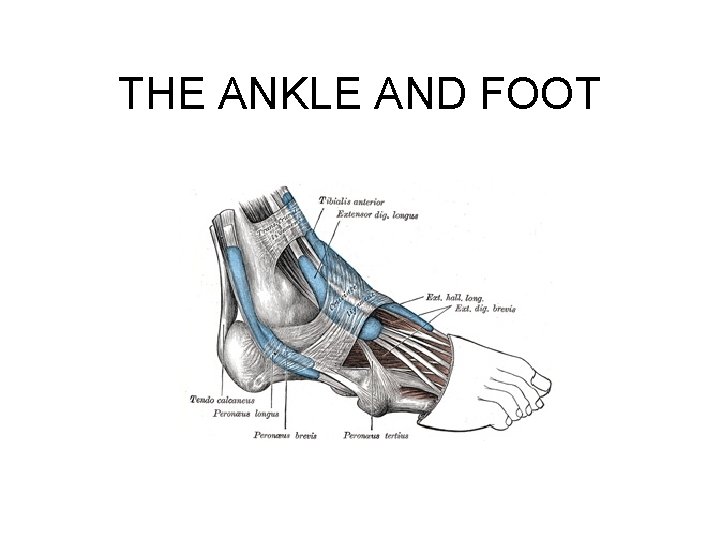

THE ANKLE AND FOOT